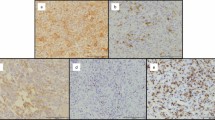

Expression of HLA-A antigens and HLA-B and -C antigens in mononuclear stromal cells were low and heterogeneous in 68% (56 of 83) and 53% (45 of 84) of the tumors, respectively. Similarly, expression of HLA-A antigens and HLA-B and -C antigens in multinucleated giant cells were low and heterogeneous in 65% (49 of 75) and 73% (56 of 77) of the tumors, respectively. There was no difference in the percentage of HLA-A and HLA-B and -C expression in mononuclear stromal cells (percentage difference, 1%; 95% CI, 12%–14%; p = 0.85) and multinucleated giant cells (percentage difference, 2%; 95% CI, −17% to 20%; p = 0.83). Representative staining patterns of giant cell lesions with HLA-A-specific mAb HCA2 and with HLA-B and -C specific mAb HC-10 are shown (Fig. 4). Beta 2-microglobulin expression was low and heterogeneous in 89% (75 of 84) of the mononuclear stromal cells and 51% (39 of 76) of the multinucleated giant cells. Low β2-microglobulin expression level in mononuclear stromal cells was associated with low HLA-A heavy chain (OR, 22.05; 95% CI, 4.00–121.58; p < 0.001) and low HLA-B and -C heavy chain (OR, 13.00; 95% CI, 2.79–60.49; p < 0. 001). Similarly, low β2-microglobulin expression level in multinucleated giant cells of β2-microglobulin was associated with low HLA-A heavy chain (OR, 7.81; 95% CI, 1.4–43.5; p = 0.011) and low HLA-B and -C heavy chain expression (OR, 7.81; 95% CI, 1.4–43.5; p = 0.011). Low expression of HLA-B and -C heavy chain, but not HLA-A heavy chain was associated with aggressive tumors (OR, 4.30; 95% CI, 1.50–12.35; p = 0.005) (Table 2). Similarly, low and heterogeneous β2-microglobulin expression was associated with aggressive tumors (OR, 4.67; 95% CI, 1.29–12.35; p = 0.031). However, when adjusting the data for HLA-B and -C heavy chain expression, we observed no association between low and heterogeneous β2-microglobulin and aggressive tumors (OR, 0.25; 95% CI, 0.03– 2.35; p = 0.383). HLA class II antigens were expressed by mononuclear stromal cells in 69% (58 of 84) of the giant cell lesions; the expression was scored as positive in 26% (22 of 84) lesions and heterogeneous in 43% (36 of 84). HLA class II antigen expression in mononuclear stromal cells was not associated with HLA class I antigen expression in mononuclear stromal cells. However, high expression of HLA class II in mononuclear stromal cells was associated with local tumor invasion to surrounding soft tissue (OR, 6.56; 95% CI, 1.40–30.56; Fisher’s exact test, p = 0.019). HLA class II antigen expression was low or negative in 75 of the 77 samples tested. Two samples were heterogenous and none of them had high expression. HLA class II antigen expression was not associated with HLA class I, or with either CD4+ or CD8+ T cell infiltration.

Representative chromogenic immunohistochemistry staining results of the giant cell lesions tissue microarray are shown for the five immunologic markers HLA class I HLA-A heavy chain (stained using hydroxycarboxylic acid receptors (HCA2) mAb), HLA class I HLA-B and -C (stained using HC-10 mAb), HLA class I β-2 using microglobulin (β2m) light chain (stained using namb-1 mAb), HLA class II (stained using lgii-612.14 mAb), and B7-H3 (stained using B7-H3-specific mAb 1027). Each tissue microarray core was scored as low, heterogeneous, or high if the percentage of the stained area lesion was less than 25%, 25% to 75%, and greater than 75%, respectively.

Was B7-H3 a Clinically and Immunologically Relevant Marker?

B7-H3 was expressed in all giant cell lesions (100%; n = 83). The expression was low and heterogeneous in 63% (52 of 83), heterogeneous in 60% (50 of 83), and low in 3% (two of 83); and in multinucleated giant cells in 51% (39 of 76), heterogeneous in 41% (31 of 76), and low in 10% (eight of 76) of tumors. High B7-H3 expression in mononuclear stromal cells was associated with high HLA-B and -C heavy chain expression (OR, 2.9; 95% CI, 1.16–7.33; p = 0.022), but not with HLA-A heavy chain expression. High B7-H3 expression in mononuclear stromal cells was associated with high CD8+ cell infiltration (OR, 3.64; 95% CI, 1.4–9.38; p = 0.006), but not with CD4+ cell infiltration. High B7-H3 expression in mononuclear stromal cells was associated with high HLA class II antigen expression (OR, 6.32; 95% CI, 1.70–23.50; p = 0.003). B7-H3 expression, by itself, was not associated with tumor aggressiveness as defined in Methods (OR, 1.42; 95% CI, 0.51–3.97; p = 0.50). However, high B7-H3 expression was associated with local tumor invasion (soft tissue mass) (relative risk [RR], 3.12; 95% CI, 2.13–4.54; p < 0.001). When stratifying the data according to CD8+ cell infiltration (high versus low), the association between high B7-H3 and local tumor invasion was seen only in the high CD8 T cell infiltration group (RR, 1.97; 95% CI, 1.2–4.27; p = 0.028). When stratifying the data according to the expression of B7-H3 and CD8+ tumor infiltrating lymphocytes in mononuclear stromal cells, the high B7-H3 expression combined with low CD8+ tumor infiltrating cells stratum was associated with increased risk of having an aggressive tumor when compared with low B7-H3 expression and high CD8+ tumor infiltrating cells stratum (OR, 8.89; p = 0.0491) (Fig. 5).